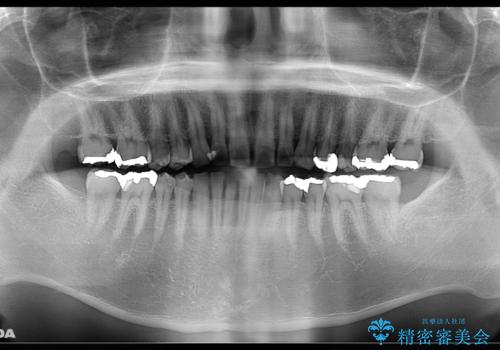

全体的なチェックも希望だったため、全体のレントゲン撮影も行いました。(レントゲン撮影は保険料金)

クリーニングで、汚れを除去した際に、古い詰め物の色がより目立ってきたため、今後やり替えすることになりました。

クリーニングを行うことで、新たな虫歯や、やり替え必要部分が見つかることがあります。